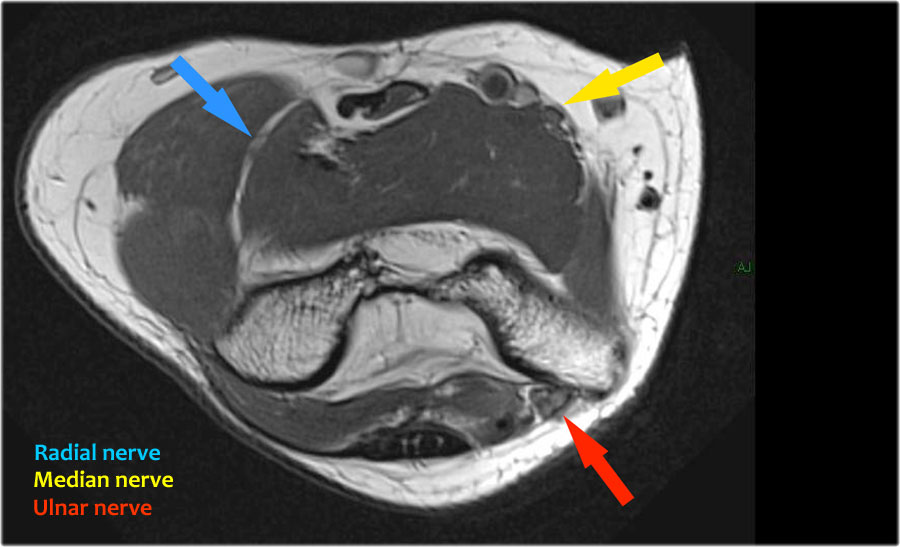

Nerves

Scroll through the images.

Ulnar nerve

Ở đây chúng ta thấy dây thần kinh trụ nằm trong ống trụ.

Bó sau của dây chằng bên trụ tạo thành sàn của ống, trong khi mạc hãm tạo thành trần của ống.

Radial nerve

Dây thần kinh quay có thể được xác định rõ nhất ở mức chỏm xương quay, nơi có thể quan sát thấy các nhánh nông và nhánh sâu trong ống xương quay (mũi tên).

This is a very consistent place to find the radial nerve.

Các nhánh quay sâu tạo thành thần kinh gian cốt sau xuyên qua cơ ngửa tại cung Frohse (mũi tên).

Median nerve

Dây thần kinh giữa đi xuống phía sau Lacertus fibrosis, là cân cơ của cơ nhị đầu và xuyên qua cơ sấp tròn.